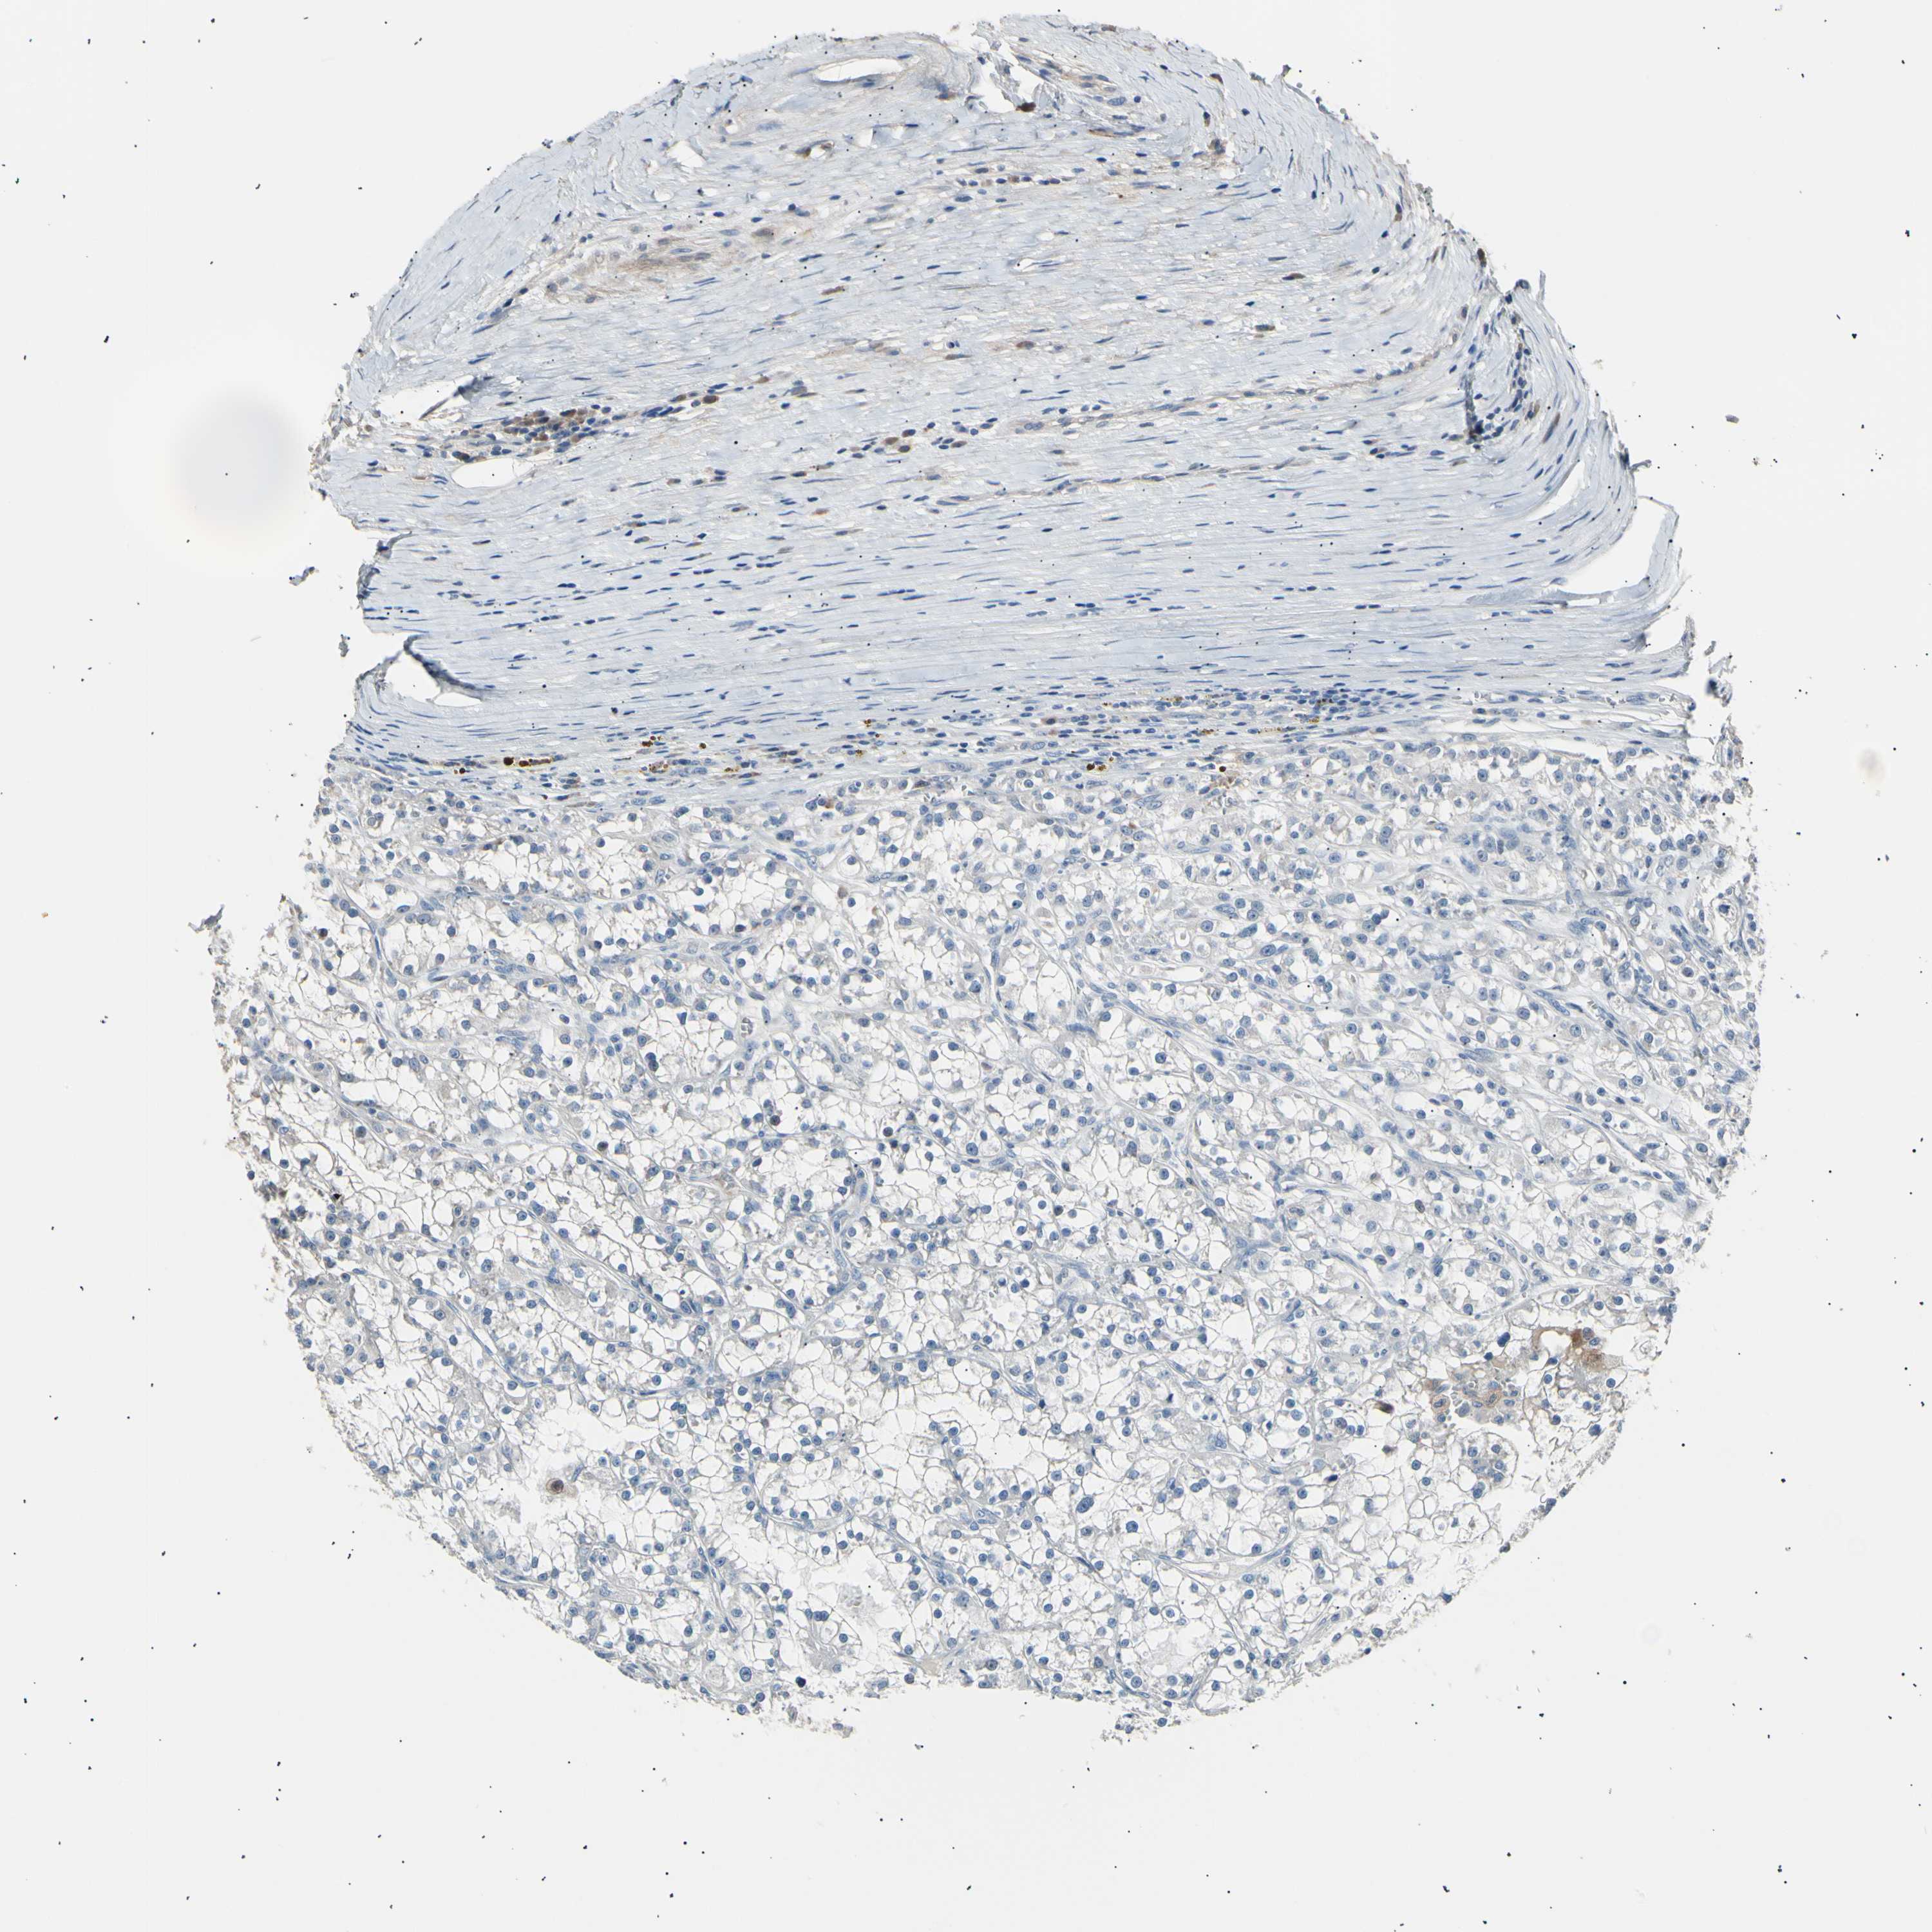

KIDNEY CHROMOPHOBE (TCGA) - Interactive survival scatter ploti

The Survival Scatter plot shows the clinical status (i.e. dead or alive) for all individuals in the patient cohort, based on the same data that underlies the corresponding Kaplan-Meier plots. Patients that are alive at last time for follow-up are shown in blue and patients who have died during the study are shown in red.

The x-axis shows the expression levels (FPKM) of the investigated gene in the tumor tissue at the time of diagnosis. The y-axis shows the follow-up time after diagnosis (years). Both axes are complimented with kernel density curves demonstrating the data density over the axes. The top density plot shows the expression levels (FPKM) distribution among dead (red) and alive patients (blue). The right density plot shows the data density of the survived years of dead patients with high and low expression levels respectively, stratified using the cutoff indicated by the vertical dashed line through the Survival Scatter plot. This cutoff is automatically defined based on the FPKM cutoff that minimizes the p-score. The cutoff can be changed by dragging the vertical line or by entering a cutoff value in the square labeled "Current cut-off".

Under the Survival Scatter plot the p-score landscape (black curve; left axis) is shown together with dead median separation (red curve; right axis). Dead median separation is the difference in median mRNA expression between patients who have died with high and low expression, respectively. It is calculated as follows: median FPKM expression of dead patients with high expression - median FPKM expression of dead patients with low expression. This is intended to aid the user in visually exploring custom cutoffs and the associated p-scores and dead median separation.

Individual patient data is displayed and can be filtered by clicking on one or more of the category buttons on the top of the page. Categories describing expression level and patient information include: high, low, alive, dead, female, male and tumor stages. The scale of the x-axis can be toggled between linear and log-scale by clicking on the "x log" button. Mouse-over function shows TCGA ID, patient information and mRNA expression (FPKM) for each patient.

& Survival analysisi

Kaplan-Meier plots summarize results from analysis of correlation between mRNA expression level and patient survival. Patients were divided based on level of expression into one of the two groups "low" (under cut off) or "high" (over cut off). X-axis shows time for survival (years) and y-axis shows the probability of survival, where 1.0 corresponds to 100 percent.

LDLR is not prognostic in Kidney Chromophobe (TCGA)

Best expression cut offi

Based on the FPKM value of each gene, patients were classified into two groups and association between prognosis (survival) and gene expression (FPKM) was examined. The best expression cut-off refers the FPKM value that yields maximal difference with regard to survival between the two groups at the lowest log-rank P-value. Best expression cut-off was selected based on survival analysis .

When clicking on this number, the vertical dashed line indicating cut-off, the interactive survival plot, and the Kaplan-Meier curve will be adjusted to show results based on the best expression cut-off.

: 22.77

TCGA RNA samplesi

RNA-seq data is reported as average FPKM (number Fragments Per Kilobase of exon per Million reads), generated by the The Cancer Genome Atlas (TCGA) .

Normal distribution across the dataset is visualized with box plots, shown as median and 25th and 75th percentiles. Points are displayed as outliers if they are above or below 1.5 times the interquartile range. FPKM values of the individual samples are presented next to the box plot.

Average pTPM 31.8

Number of samples 64